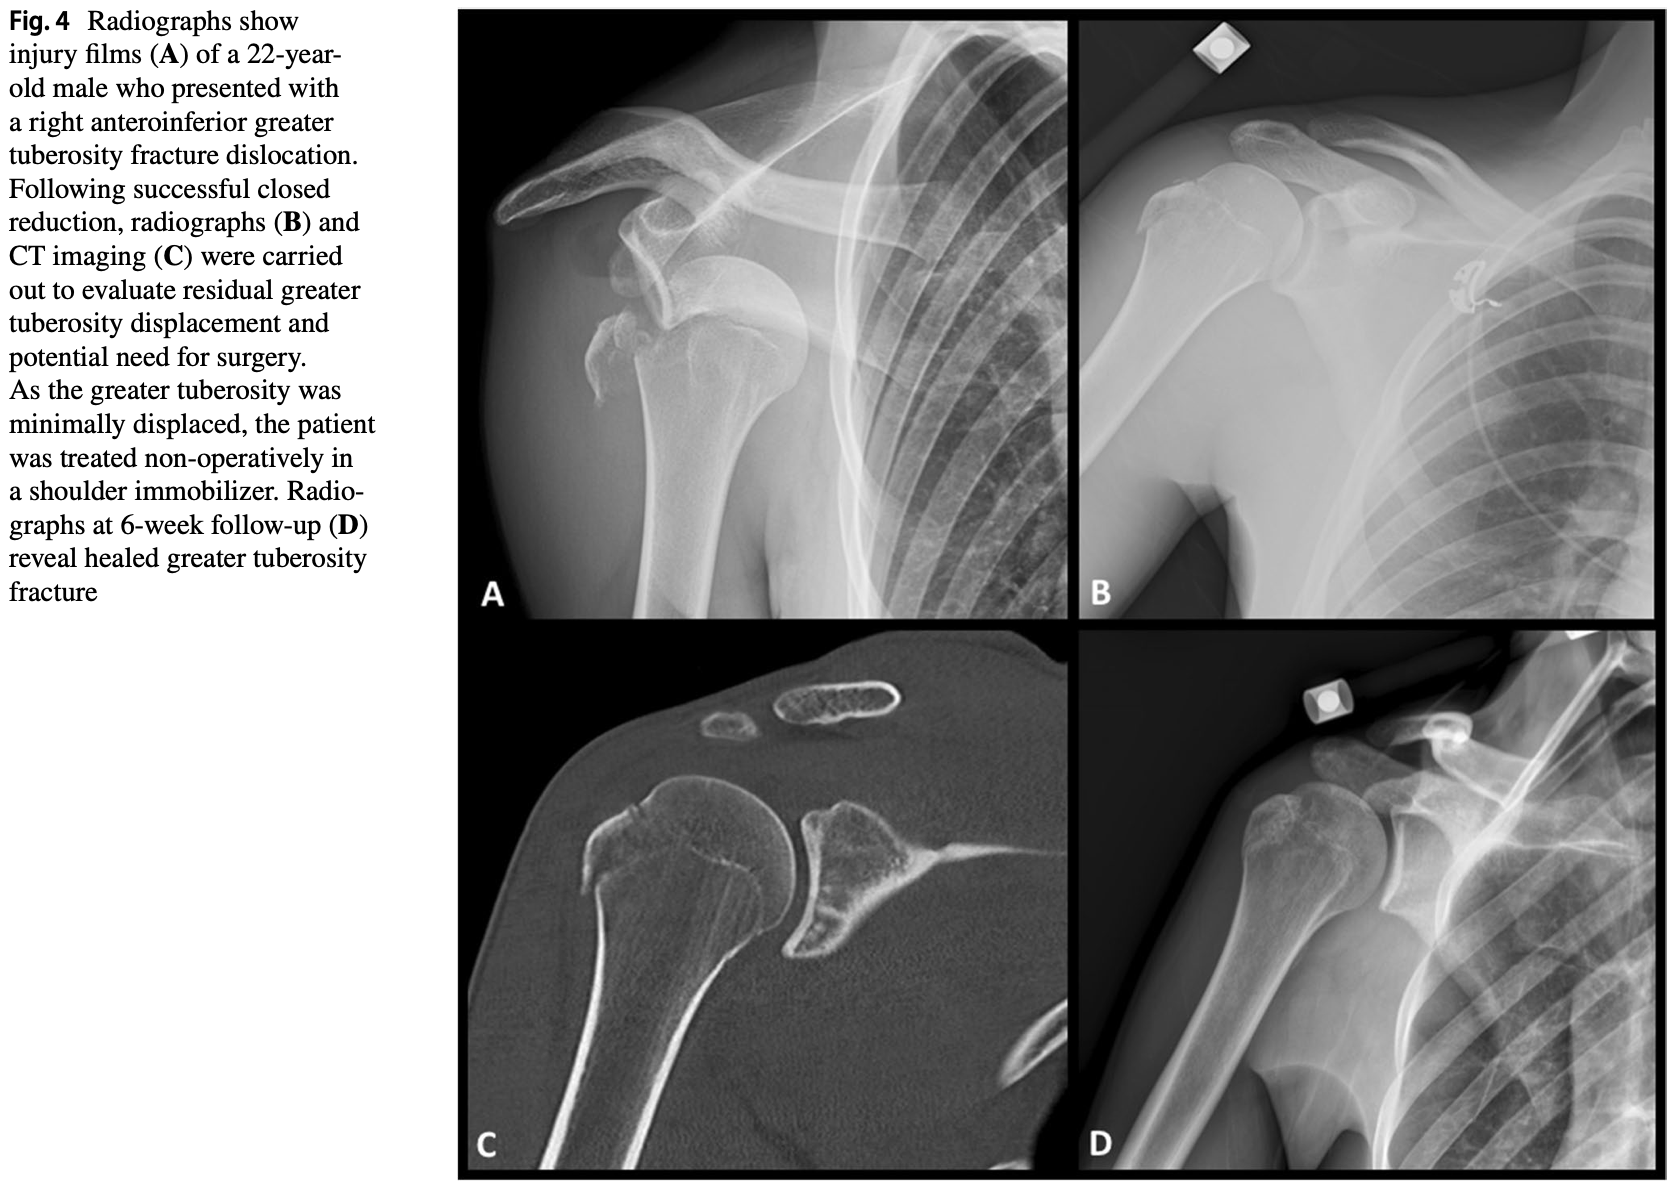

15時に来院された患者さんは, 上腕骨大結節骨折を伴う肩関節脱臼骨折.

その場で整復操作を試みましたが, 脱臼から3日が経過しており, 整復は困難.

入院していただき, 明日, 全身麻酔下で整復手術を行う方針としました.

100歳目前ではありますが, 認知機能に問題はなく, 受け答えは明瞭.

これまで入院・手術歴もないとのことで, 年齢だけでは測れない若々しい患者さんでした.